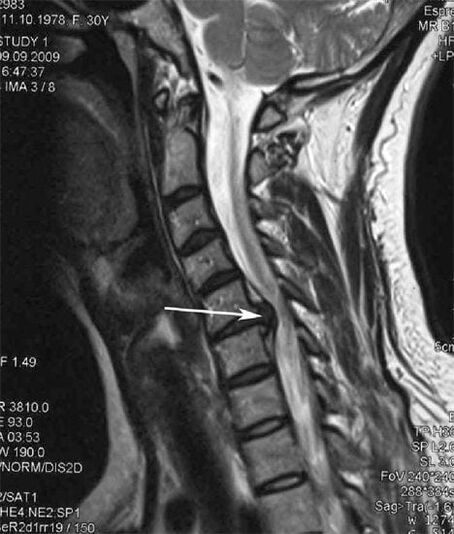

V počiatočných štádiách sa osteochondróza zisťuje pomocou MRI. Neskôr môže byť patológia diagnostikovaná pomocou rádiografie. Na röntgenových snímkach krčnej chrbtice sa prejavuje zmenšenie vzdialenosti medzi stavcami, patologické zmeny fazetových kĺbov a osteofytóza.